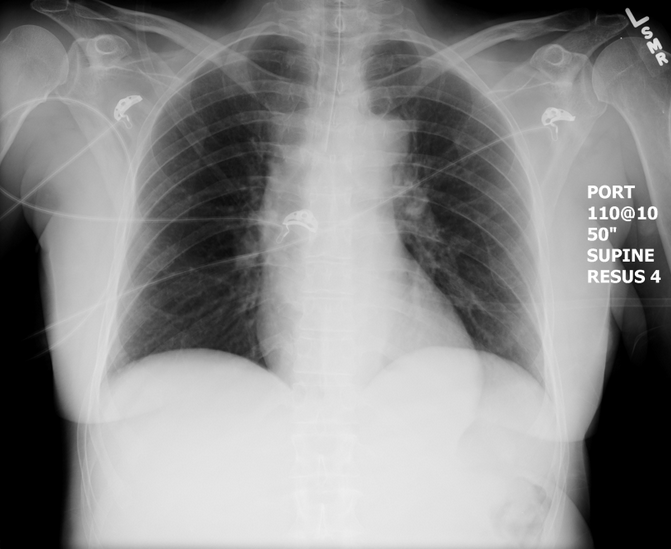

Post-intubation CXR for Patient 2 found here:

(CXR source: https://emcow.files.wordpress.com/2012/11/normal-intubation2.jpg)